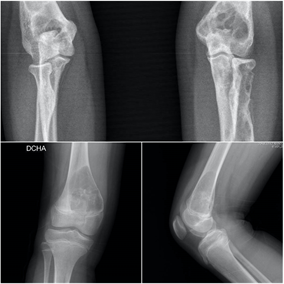

Los sarcomas óseos son tumores óseos muy infrecuentes, con una incidencia aproximada de 1 caso por cada 100.0000 habitantes. El Osteosarcoma es el tumor óseo primario maligno más frecuente en la infancia, seguido por el el Sarcoma de Ewing. En las radiografías se suelen evidenciar lesiones líticas, permeativas, con destrucción ósea, reacción perióstica y afectación del los tejidos blandos cercanos. Estos pacientes ,además de dos proyecciones radiográficas, precisarán estudios complementarios de imagen, biopsia, estudio de extensión para descartar diseminación pulmonar, y valoración multidisciplinar. La cirugía oncológica de salvamento de extremidad y reconstrucción es la técnica de elección.

Los sarcomas óseos son tumores primarios malignos muy raros que afectan fundamentalmente a niños y adolescentes, aunque también puede aparecer en pacientes mayores de 65 años, en relación con otras enfermedades o radioterapia. Debemos sospechar la presencia de un tumor maligno primario de hueso en pacientes con imágenes radiológicas de apariencia agresiva, como márgenes mal definidos, lesiones líticas con patrón permeativo, destrucción de las corticales, reacción perióstica e invasión de los tejidos blandos. Si detectamos una lesión de este tipo debemos siempre realizar una valoración multidisciplinar por equipos especializados en Traumatología oncológica y Oncología.